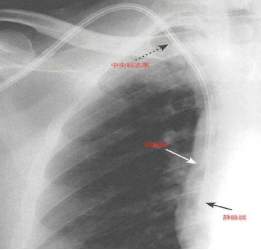

吴某某 男 57岁,尿毒症透析患者,左前臂自体动静脉内瘘,血流量不足150ml/min,不能满足透析需要。

一般情况下,内瘘流量不足多为血管内狭窄或血栓形成导致,将形似“气球”的球囊扩张导管放到血管腔内狭窄或血栓部位,给予一定压力注入液体后扩张病变部位,血管通畅,术后就可以穿刺透析了。这种微创手术相对传统开刀手术而言,最大限度保留血管资源,减少手术创伤。

DSA下行血管造影及内瘘PTA手术过程